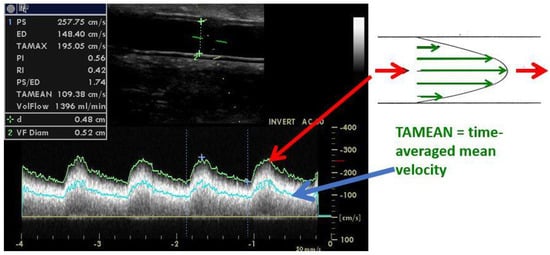

5. Significant Stenosis Definition by Ultrasonography